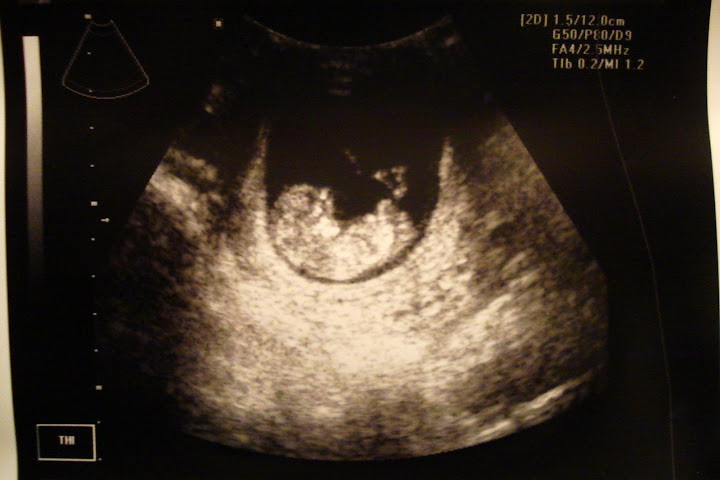

Anywho, not hearing the h/b necessitated a trip to the u/s machine! I can't complain! It was soooo neat seeing a baby-shaped blob instead of a blob-shaped blob :)

Here she (he?) is! Pretty dang cute, if I don't say so myself. (Head is to the left, and this is a profile shot).